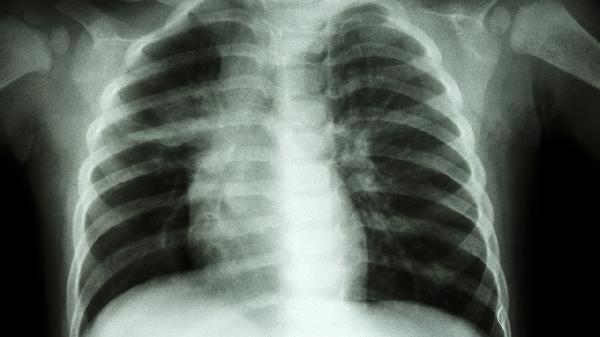

重度畸形可能限制肺扩张,引发反复呼吸道感染或运动耐力下降。肺功能检查显示限制性通气障碍时,需考虑胸腔镜辅助微创手术。术后呼吸训练包括腹式呼吸、吹气球练习。